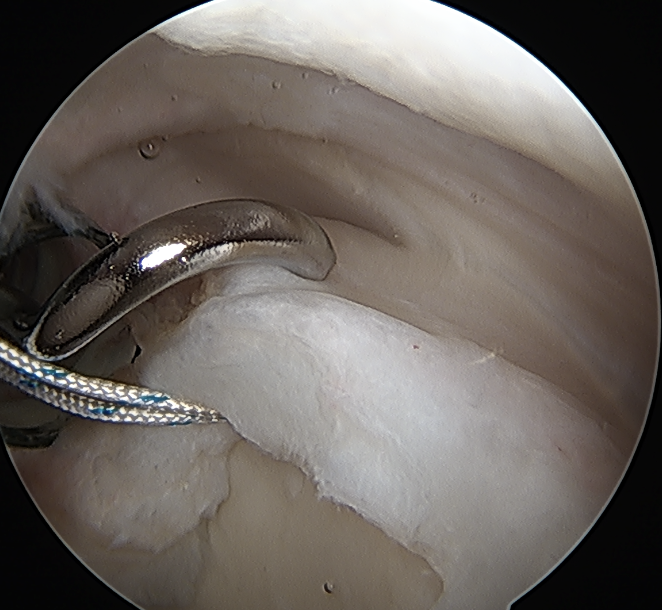

SLAP repair + arthroscopic suprapectoral biceps tenodesis

Technique

Beach chair

- tag biceps tendon with high strength suture and release

- repair superior labrum with one or two anchors

- anchor biceps tendon into bicipital groove

Tag biceps through portal just anterior to supraspinatus tendon

Release biceps and perform superior labral repair

Anchor biceps tendon into bicipital groove